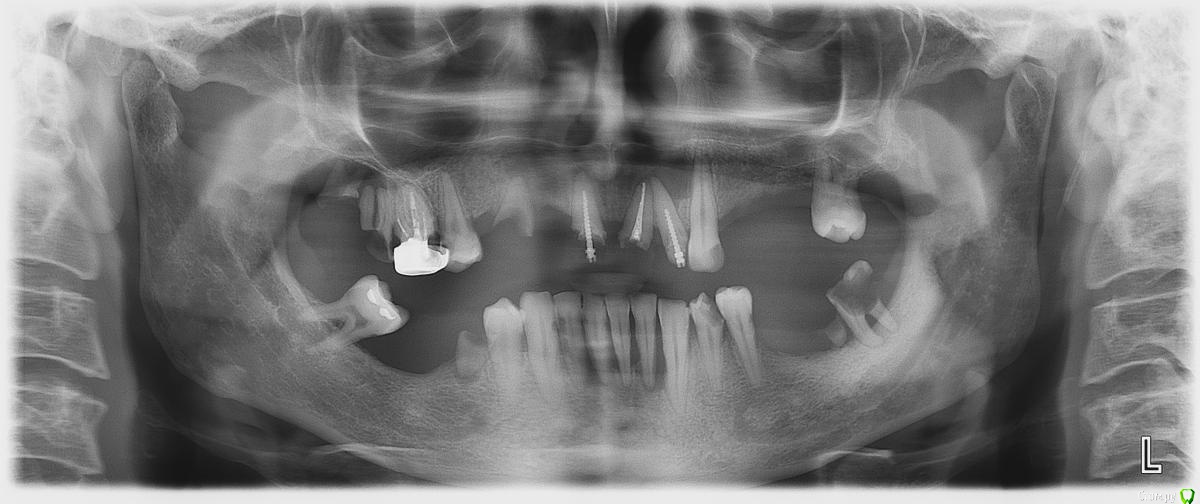

-SAE-Dantist_32 Опубликовано 17 июля, 2015 Поделиться Опубликовано 17 июля, 2015 не знаю как поступить с 1.1 2.1 сносить? Ссылка на комментарий

krokomot Опубликовано 17 июля, 2015 Поделиться Опубликовано 17 июля, 2015 Сносите. При их протезировании мало того, что коронки получатся оч длинными так еще и широкими потому как расстояние между корнями не благоприятствует их протезированнию. Поэтому в лучшем случае будут проблемы с десной. Ссылка на комментарий

-SAE-Dantist_32 Опубликовано 17 июля, 2015 Автор Поделиться Опубликовано 17 июля, 2015 а как быть с 3.3?c одной стороны жалко с другой понемаеш что нужно сносить) Ссылка на комментарий

krokomot Опубликовано 17 июля, 2015 Поделиться Опубликовано 17 июля, 2015 Планируется имплантация? Ссылка на комментарий

-SAE-Dantist_32 Опубликовано 17 июля, 2015 Автор Поделиться Опубликовано 17 июля, 2015 да в планах имплантация,правда не придумал карту сколько куда) Ссылка на комментарий

Doc.IQ Опубликовано 17 июля, 2015 Поделиться Опубликовано 17 июля, 2015 При имплантировании тотально удалился бы..если имплантация не планируется оставил бы 16,23,34,35,43,44..остальное на вылет.. Ссылка на комментарий

krokomot Опубликовано 17 июля, 2015 Поделиться Опубликовано 17 июля, 2015 Если имплантация все сомнительное вон и мешающее Ссылка на комментарий